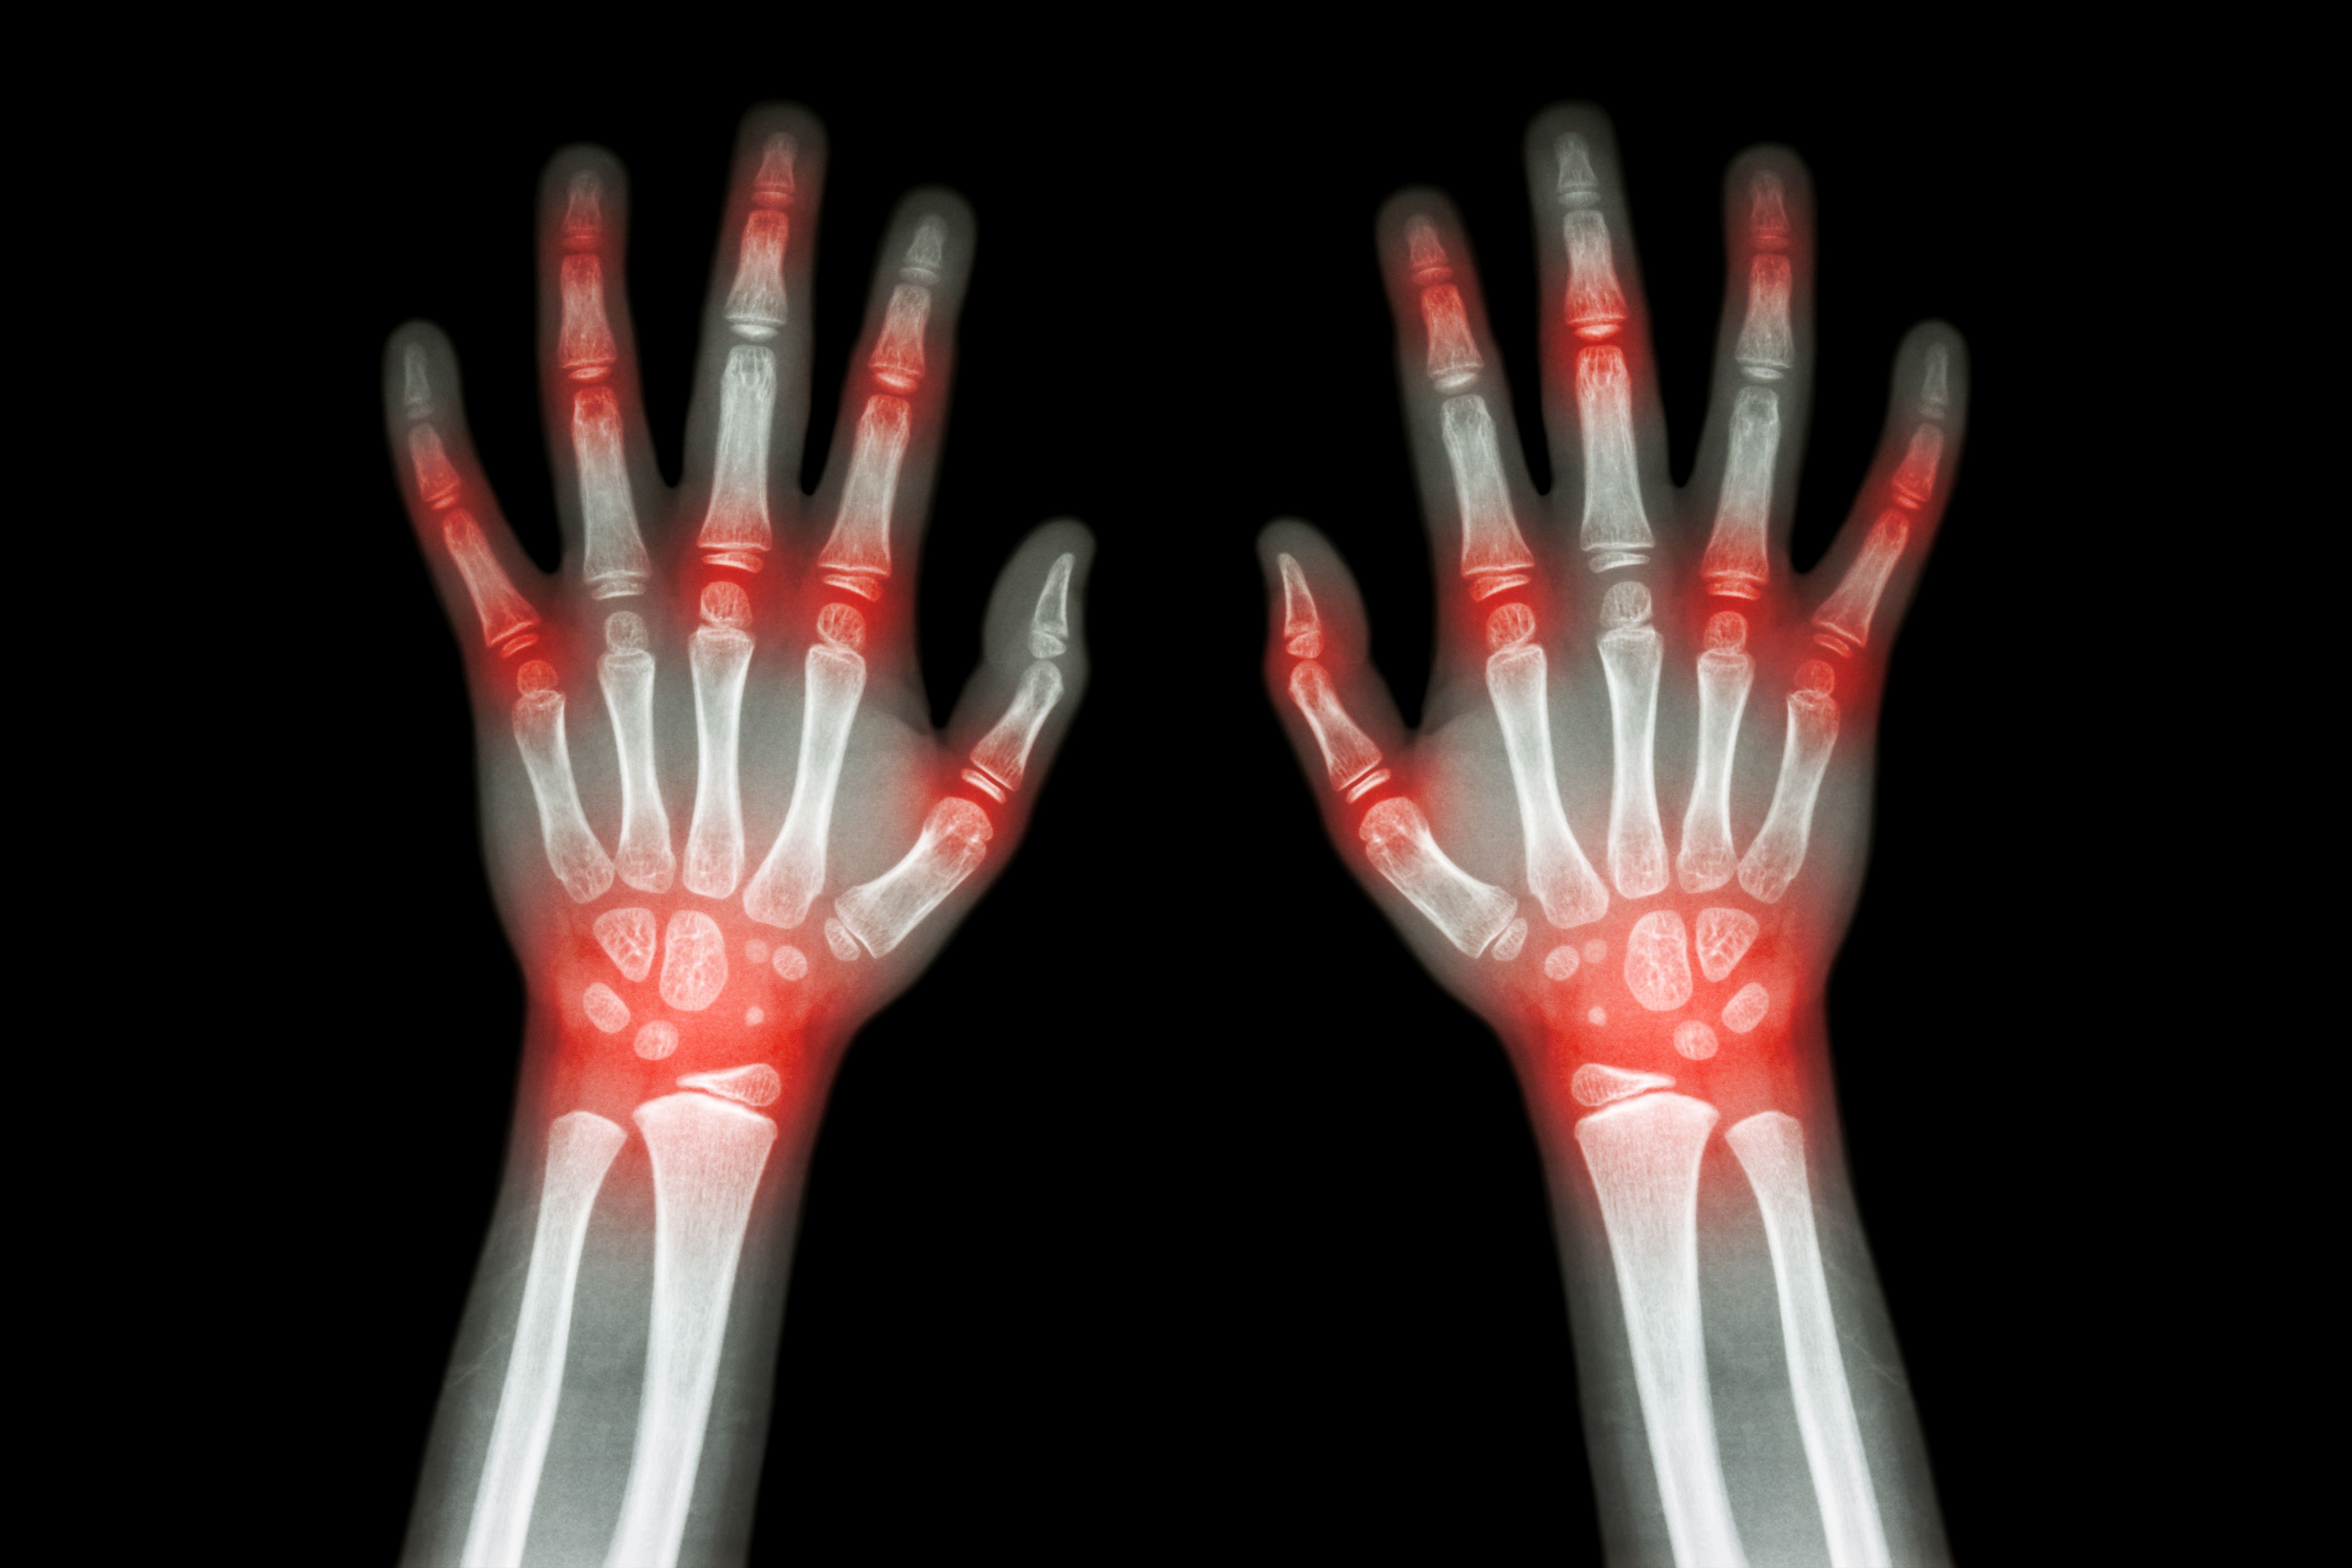

A laboratory test that he said is useless in children as a diagnostic tool for rheumatoid disease is the measurement of rheumatoid factor. Although this autoantibody detects about 70% of adults with rheumatoid arthritis, it has a very low sensitivity in children. In addition, the test is not needed to make the diagnosis of juvenile idiopathic arthritis because the signs and symptoms of disease are sufficient for accurate diagnosis.

Over the last decade, little has changed in the laboratory options available to physicians when screening children for potential rheumatologic conditions. A commercial assay for a novel autoantibody associated with inflammatory arthritis, anticyclic citrullinated peptide (anti-CCP), has been developed and is available for general use. Anti-CCP antibody is found in fewer than 10% of children with juvenile idiopathic arthritis (JIA), correlates highly with the presence of rheumatoid factor (RF), and portends a more aggressive disease course. Like RF, anti-CCP testing is not recommended as a screening tool for JIA but should rather be used as an indicator of prognosis following the diagnosis of arthritis. Serologic testing for antineutrophil cytoplasmic antibody (ANCA), associated with certain forms of chronic vasculitis, has become more widely available.